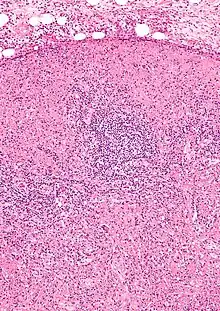

Micrograph of a lymph node with Kikuchi disease showing the characteristic features (abundant histiocytes, necrosis without neutrophils). H&E stain.